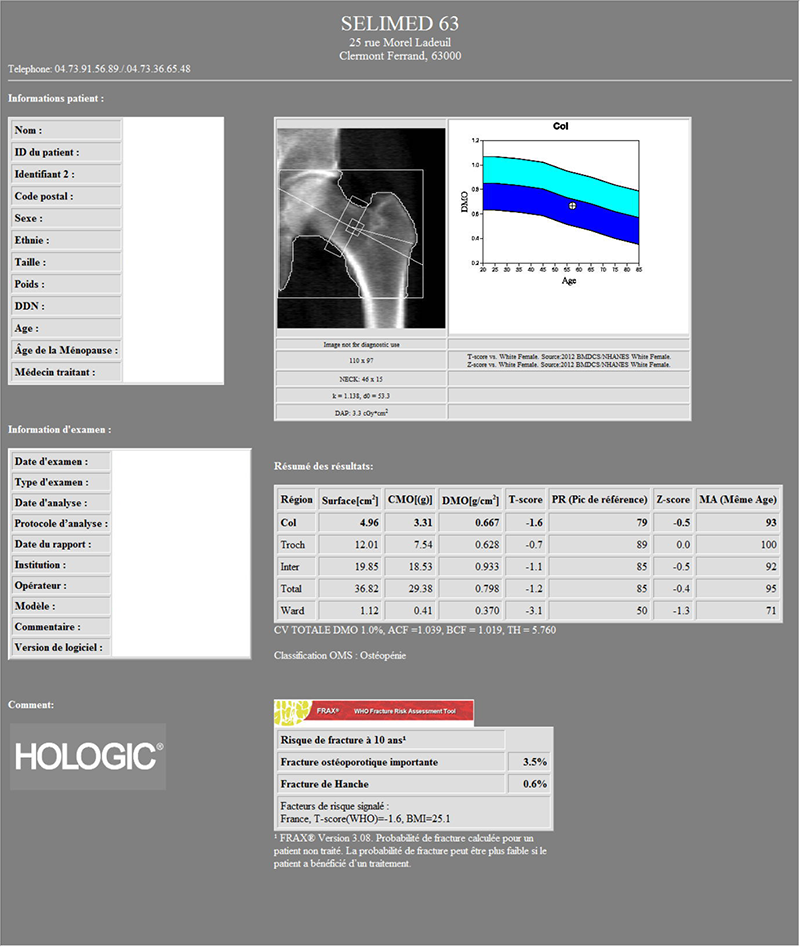

Pour ceci, on mesure l'atténuation subie par le faisceau de rayons X après sa traversée des tissus osseux. On établit ainsi un score (T-score et Z-score). Schématiquement, plus l'os est dense (donc riche en calcium et solide), plus le faisceau est atténué.